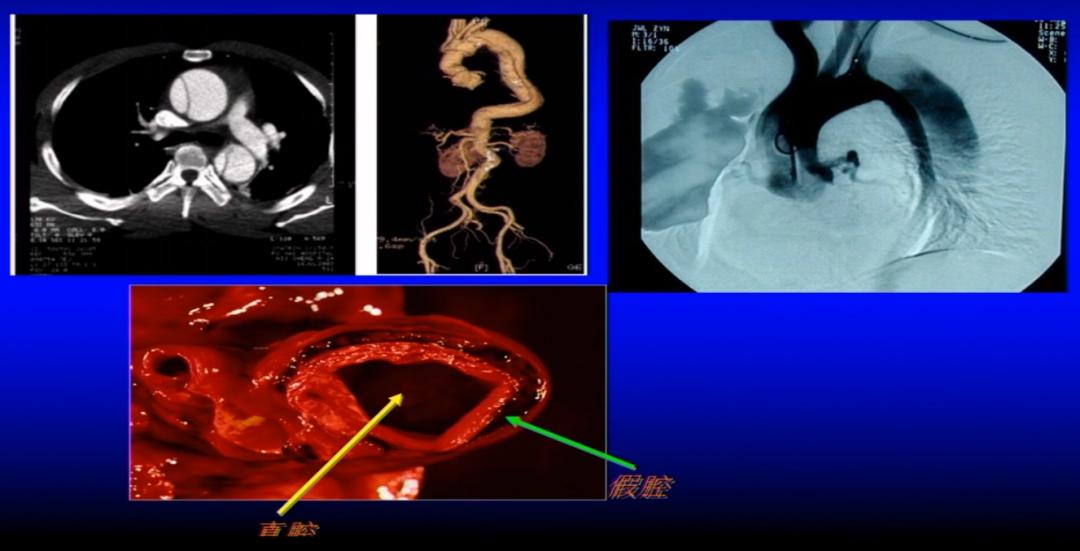

主动脉夹层是指主动脉腔内的血液从主动脉内膜撕裂口进入主动脉中膜,并沿主动脉长轴方向扩展,造成主动脉真假两腔分离的一种病理改变,因通常呈继发瘤样改变,故将其称为主动脉夹层动脉瘤(图4)。

图4 主动脉夹层的病理改变

图5 主动脉夹层的影像学表现